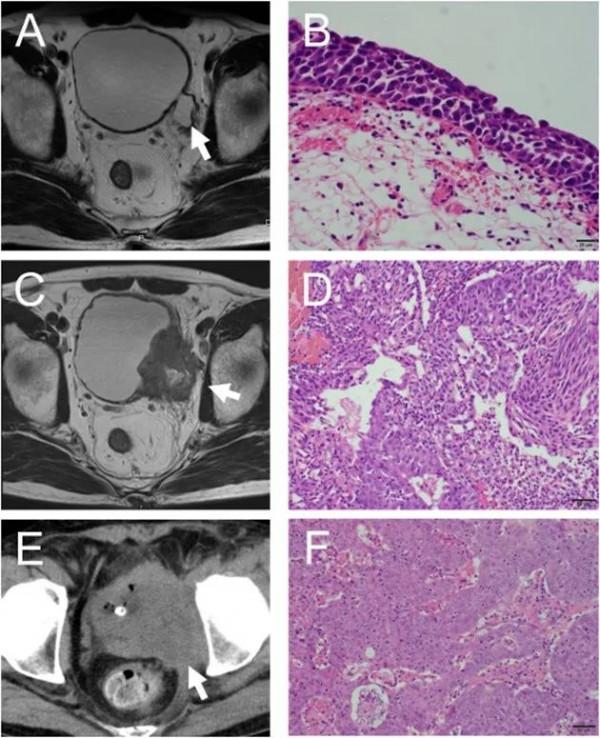

日本男性,69歲,主訴肉眼血尿。57歲時有非肌層浸潤性膀胱癌病史。當時MRI顯示膀胱憩室但膀胱內無腫瘤,經尿道膀胱腫瘤電切術(TURBT)獲取標本的病理結果為僅在膀胱憩室的原位癌(圖1A和B)。TURBT之後患者沒有接受額外治療。MRI顯示區域性浸潤性T4膀胱癌,侵犯了源於憩室的髂內動脈分支(圖 1C)。行TURBT和病理檢查提示高級別浸潤性尿路上皮癌(UC)(圖1D)。

患者拒絕全膀胱切除術,選擇保留膀胱治療。患者先接受了順鉑+吉西他濱+放療(60 Gy/30 fr)化療,但TURBT後病理結果再次提示殘留病灶高級別浸潤性尿路上皮癌。隨後患者接受甲氨蝶呤+長春鹼+表柔比星+卡鉑二線化療,但疾病仍繼續進展(圖1 E、F),患者出現左腿疼痛和腫脹。巧合的是,當時帕博利珠單抗剛好在日本獲批,因此開始接受帕博利珠單抗治療。

圖1 放化療前後的影像學和病理學結果。(A) 12年前的MRI成像結果。箭頭表示膀胱憩室;膀胱內無明顯腫瘤;(B) 12年前TURBT樣本病理學結果;(C) MRI成像結果。箭頭表示癌症位於膀胱憩室並已侵入骨盆和左髂動脈;(D) 放化療前TURBT樣本病理學結果;(E)放化療CT掃描結果,箭頭表示疾病進展;(F) 放化療後 TURBT樣本病理學結果。